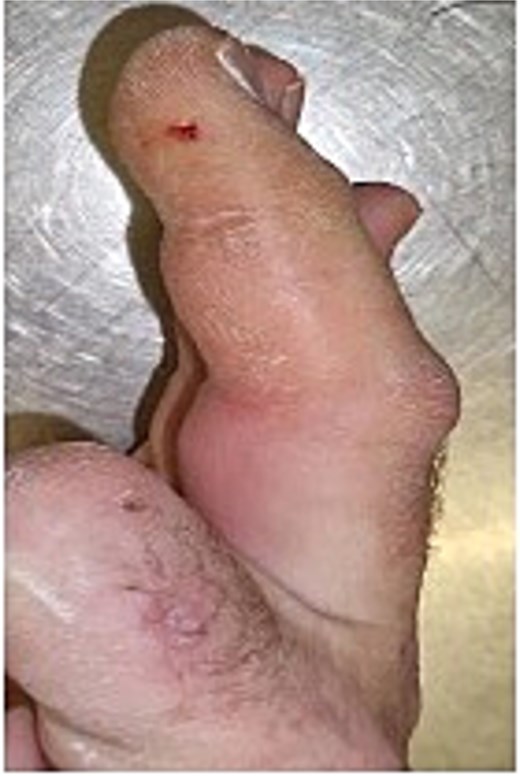

Initial presentation (Fig. 4) with accompanying X-ray (Fig. 5) and intra op image during first debridement (Fig. 6).

Image of patient two, showing his digit at presentation displaying very small puncture wound on lateral volar surface of his digit.